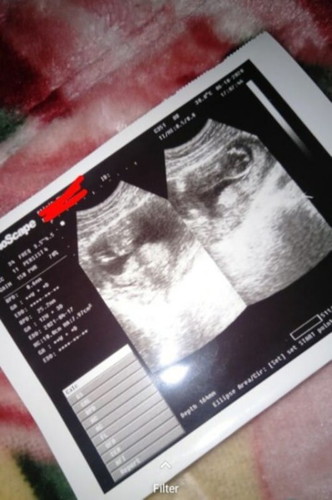

Hamil 12w 5d

Apa BPD nya itu normal bun? 25,2mm untuk ukuran 12w 5d

bpd panjang dari pelipis kanan ke kiri. kalau normal engga nya hrsnya tanya dokter nya. soalnya saya usg 13w posisi baby lg salto ga bs ukur bpd, jadi ngukur AC sama FL aja.

Baca lagisy aja waktu hamil 14w bpd nya 28,9 bun,dan dok blg normal2 aja